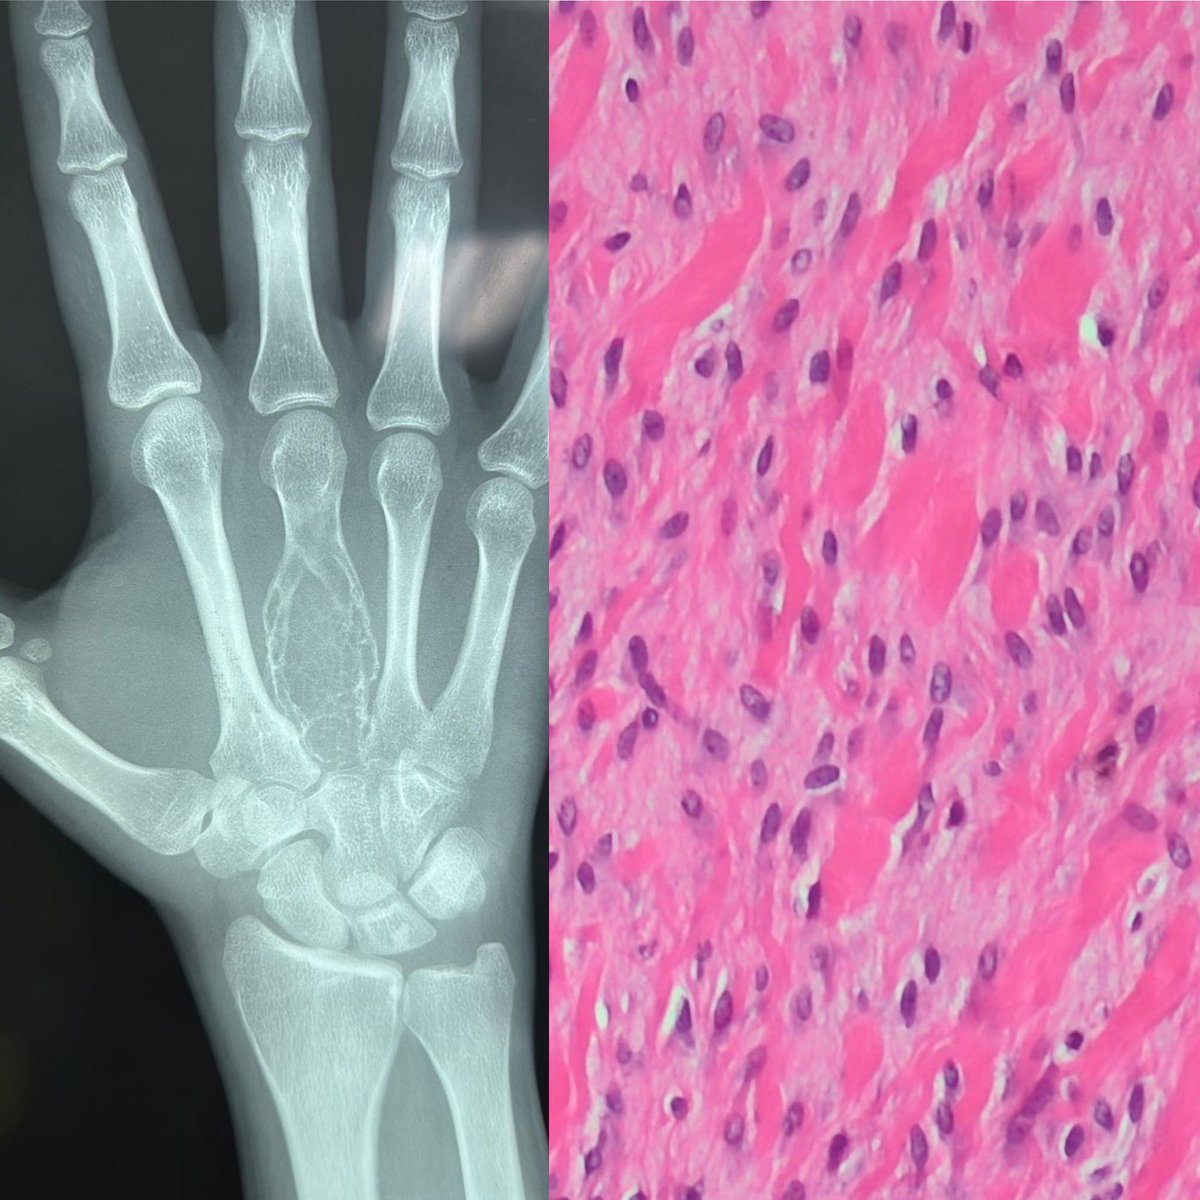

The frozen section